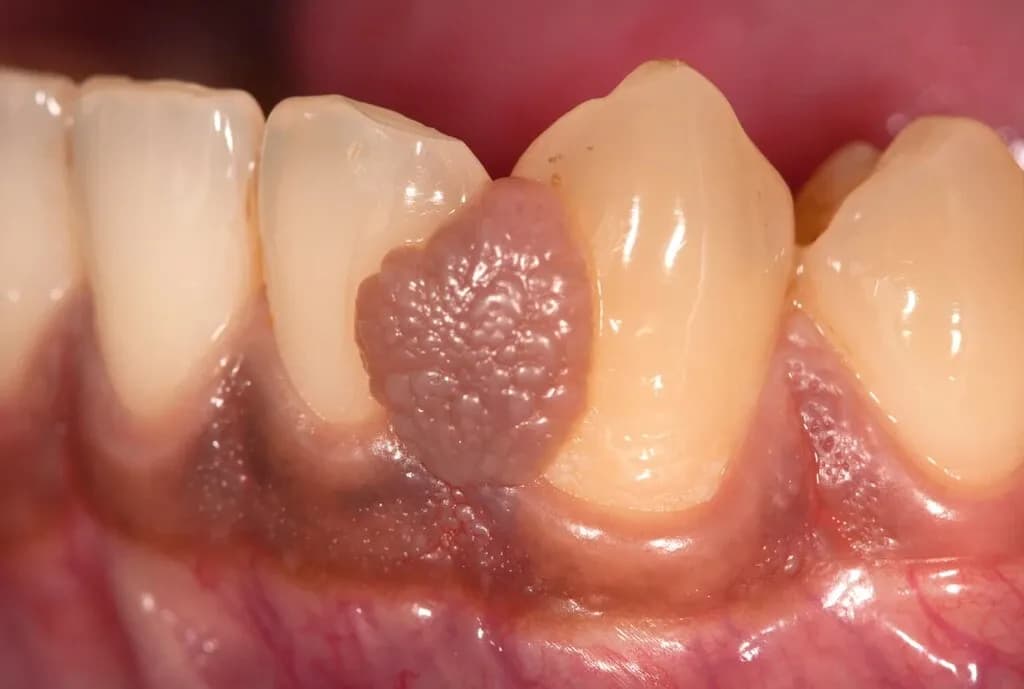

Objawy, które wymagają pilnej wizyty u stomatologa

Niektóre objawy związane z opuchlizną dziąseł mogą wskazywać na poważniejsze problemy zdrowotne, które wymagają natychmiastowej interwencji stomatologicznej. Silny ból w okolicy dziąseł lub zębów często oznacza, że może występować infekcja lub stan zapalny, który nie ustępuje. Gorączka to kolejny sygnał alarmowy, który może sugerować, że organizm walczy z infekcją, co wymaga oceny przez specjalistę. Utrzymująca się opuchlizna przez dłuższy czas, która nie reaguje na domowe metody leczenia, również powinna skłonić do wizyty u dentysty, aby uniknąć poważnych komplikacji.

W przypadku wystąpienia któregokolwiek z tych objawów, należy jak najszybciej udać się do stomatologa. Ignorowanie tych symptomów może prowadzić do poważniejszych problemów, takich jak ropnie, które mogą wymagać bardziej skomplikowanego leczenia. Wczesna interwencja jest kluczowa dla zapobiegania dalszym komplikacjom zdrowotnym.

Jakie zabiegi stomatologiczne mogą być potrzebne

W przypadku opuchlizny dziąseł, stomatolog może zalecić kilka różnych zabiegów w zależności od przyczyny problemu. Skaling poddziąsłowy to jedna z najczęstszych procedur, która polega na usunięciu kamienia nazębnego i płytki bakteryjnej, co pomaga w leczeniu zapaleń dziąseł. W niektórych przypadkach, gdy infekcja jest poważna, może być konieczne leczenie kanałowe, które polega na usunięciu zakażonej tkanki z wnętrza zęba. Dodatkowo, stomatolog może zalecić leki przeciwzapalne lub antybiotyki, aby pomóc w walce z infekcją.